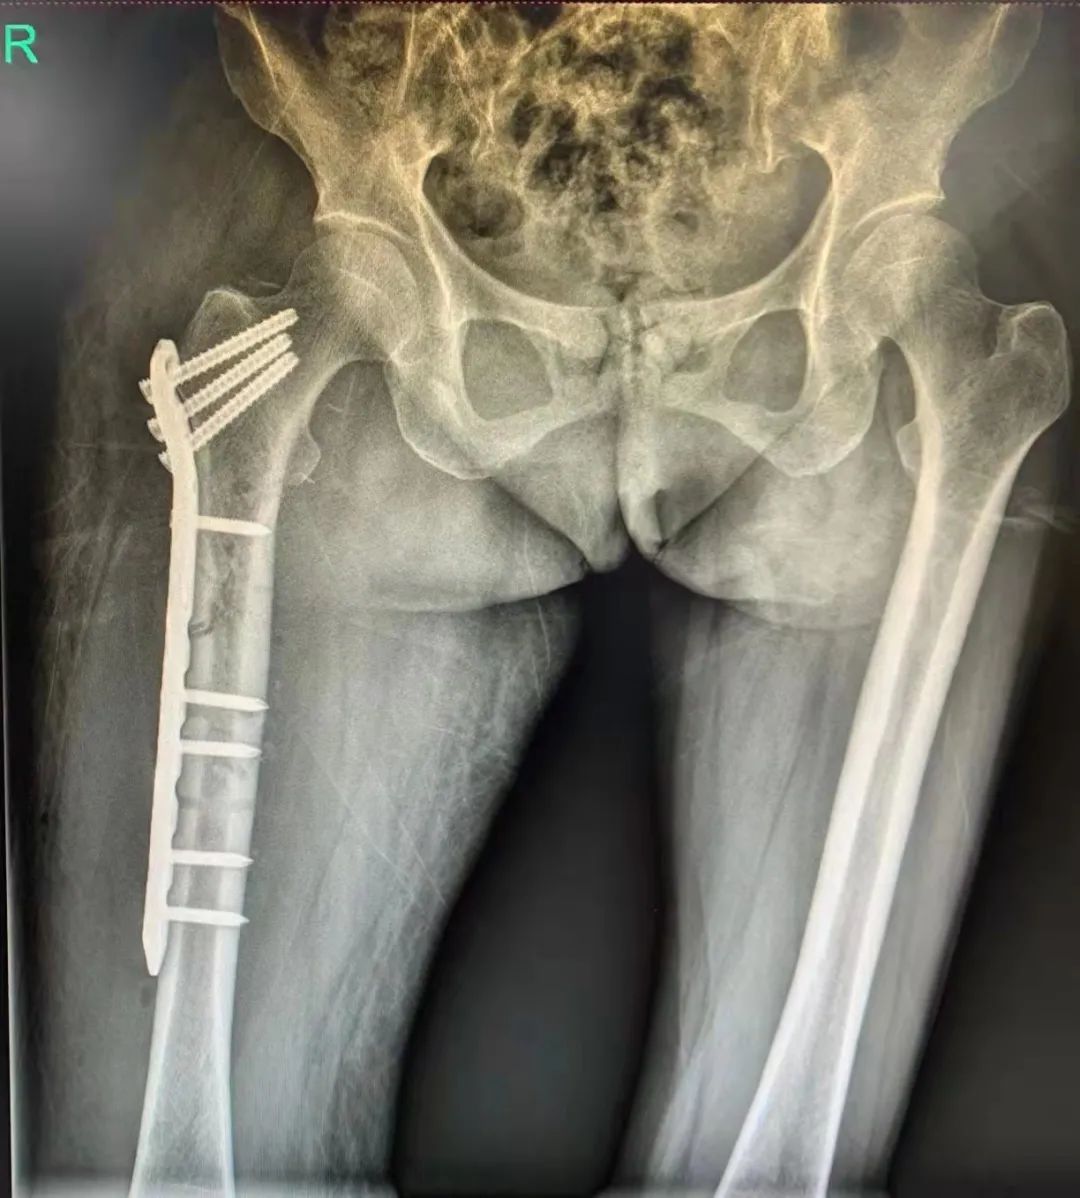

在麻醉医师团队、手术室护理团队的大力支持和默契配合下,手术顺利完成。术后第一天患者疼痛明显改善,能床上坐立,复查X线示骨折对位对线良好,内固定物位置理想。

▲术后X线